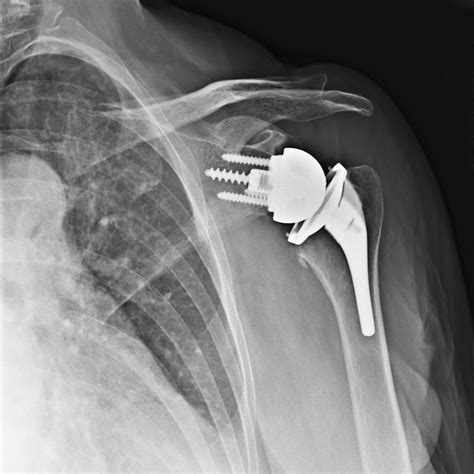

Shoulder replacement surgery, also medically referred to as shoulder arthroplasty, is a surgical intervention where the damaged parts of the shoulder joint are removed and replaced with artificial components, known as prostheses. The shoulder is a ball-and-socket joint, and when the smooth cartilage that allows the bones to glide against each other wears away, the result is painful bone-on-bone contact.

During the procedure, an orthopedic surgeon replaces the humeral head (the ball) with a metal ball and replaces the glenoid (the socket) with a smooth plastic cup. The goal is to eliminate pain and allow the patient to return to normal functioning with a stable and comfortable joint.